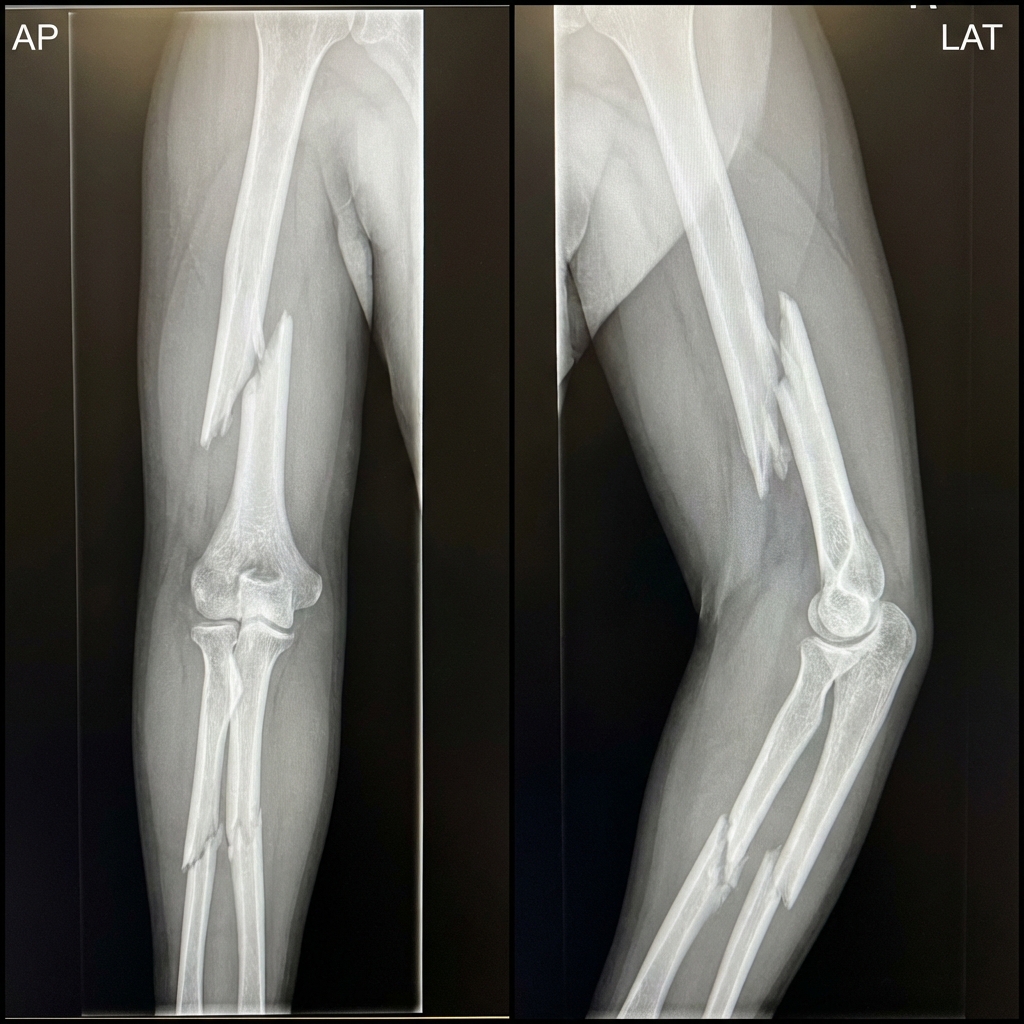

AP and lateral radiographs demonstrating displaced midshaft humerus fracture with spiral pattern and displaced both-bone forearm fracture in the same limb. The elbow joint appears concentrically reduced but without bony continuity to either shoulder or wrist. This is a floating elbow injury - a high-energy pattern with significant complication risk.

Define this injury pattern and what are your initial assessment priorities?

What is the significance of this injury pattern and what complications should you anticipate?